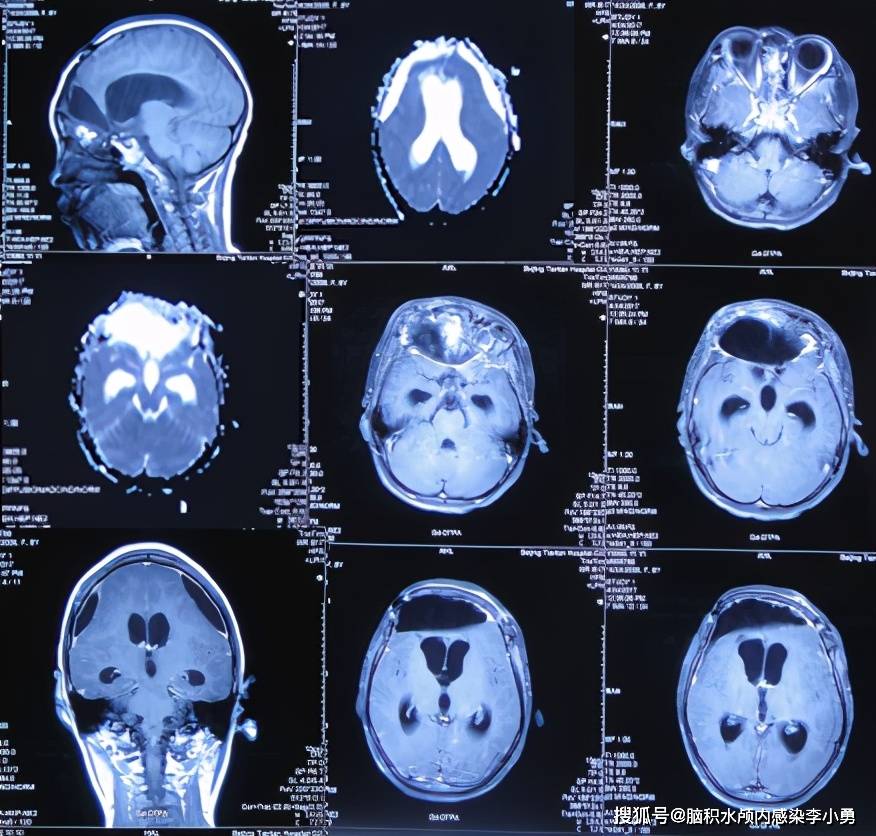

基本上价格差不多正脑体积减小拍片多少钱,275不带加强以上是3甲医院正脑体积减小拍片多少钱的价格正脑体积减小拍片多少钱,反正不差那几十还是上大医院正脑体积减小拍片多少钱,总体来说设备都差不多,就是看医生技术了。...